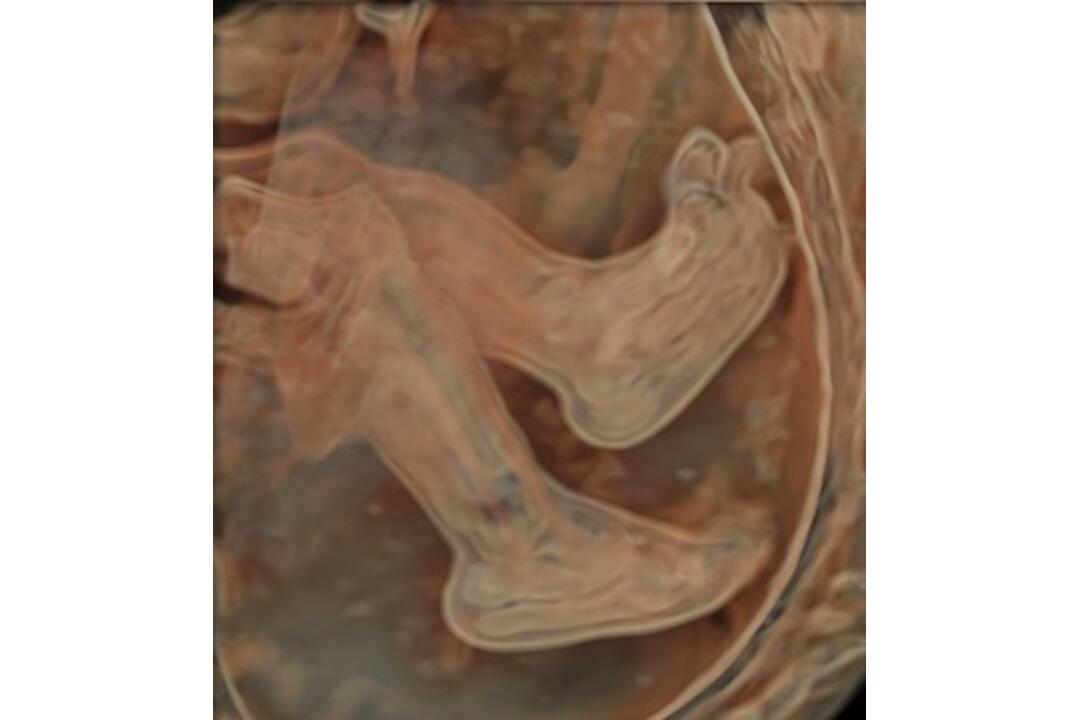

FOTO: Šačianska nemocnica predstavila najmodernejší ultrazvuk

FOTO: Šačianska nemocnica predstavila najmodernejší ultrazvuk, foto 5

Nemocnica Agel Košice – Šaca

Zdroj: Nemocnica Agel Košice – Šaca